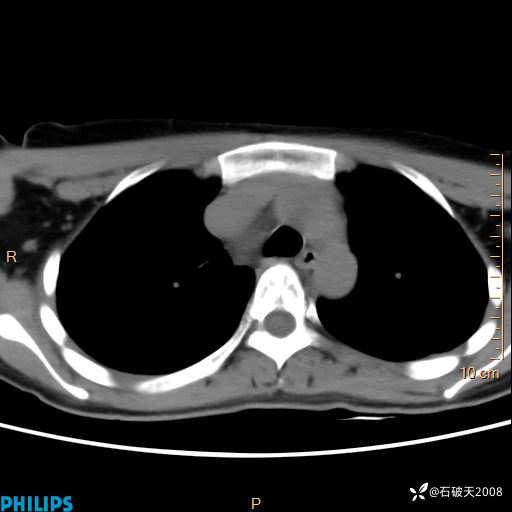

冠状位